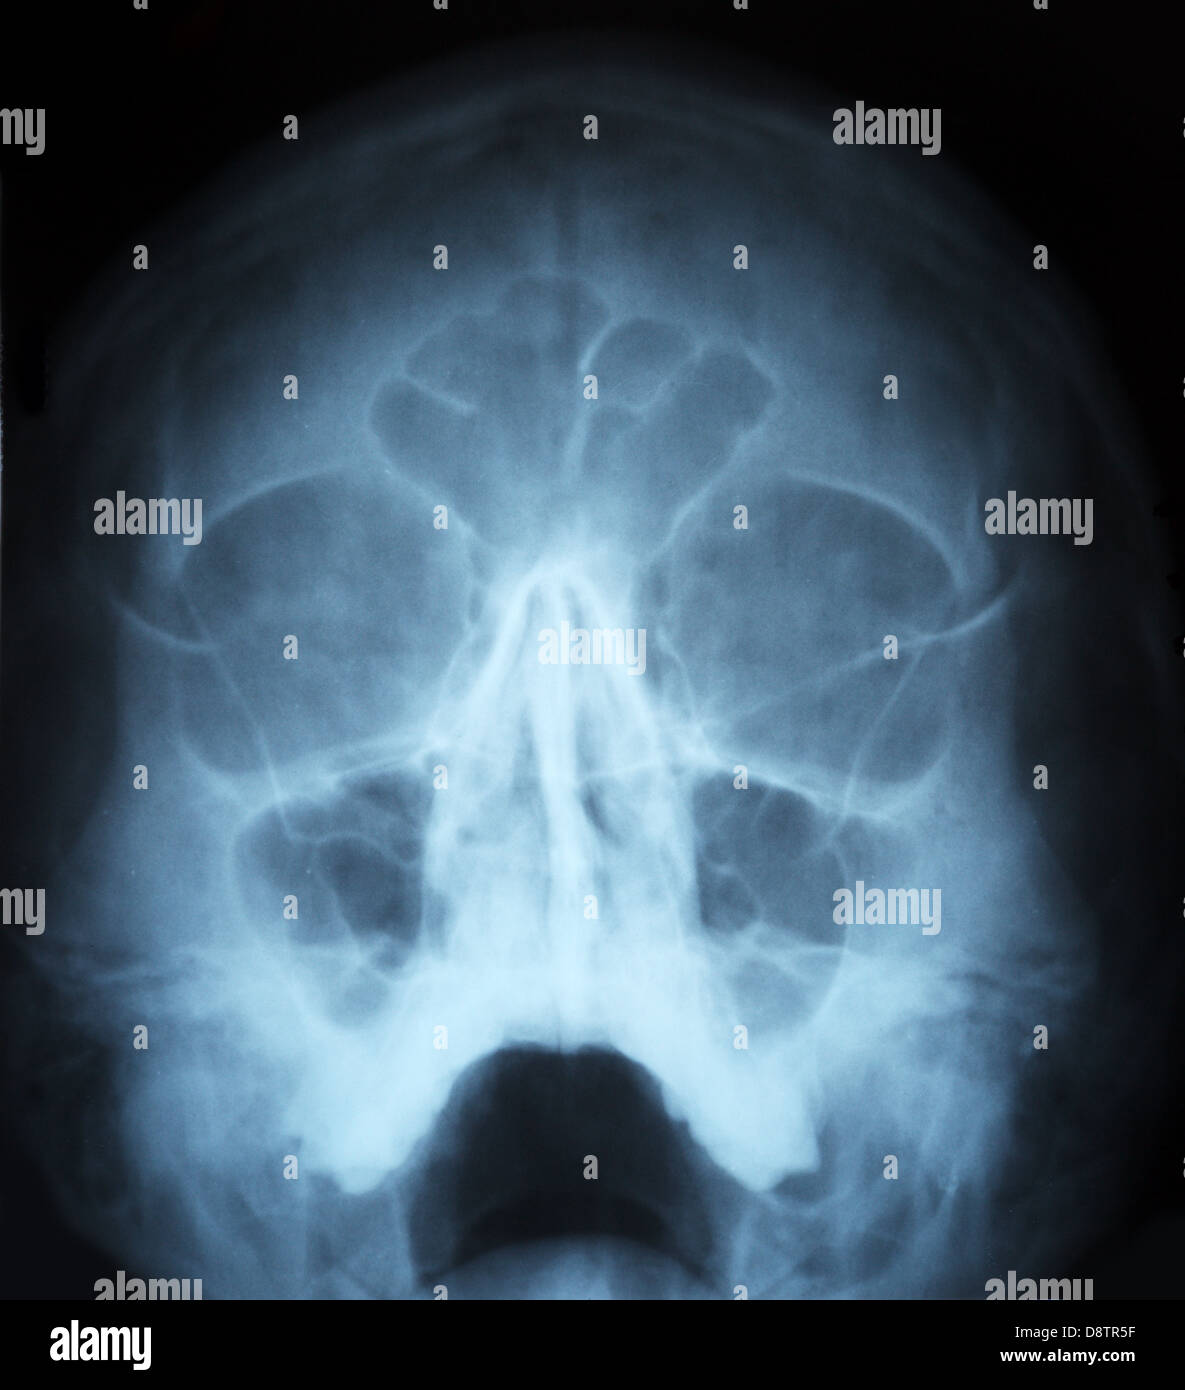

Prepare to be captivated by List, a showcase of real human skull front view black and white imagery powered by ieltschampions.edu.vn. More related visuals are below.

real human skull front view black and white

Posts: real human skull front view black and white